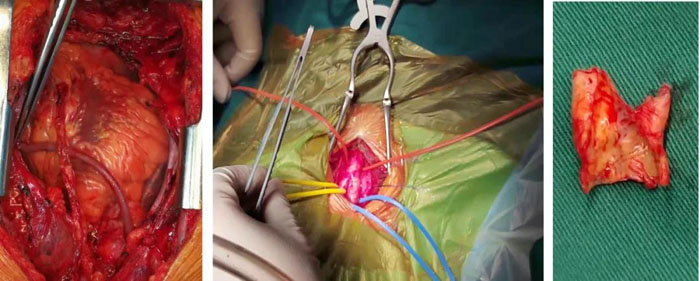

術中情況

施行同期頸動脈內(nèi)膜剝脫手術和冠狀動脈搭橋手術,對于手術團隊的要求比較高,需要麻醉醫(yī)師、體外循環(huán)醫(yī)師、器械/巡回護士、術后監(jiān)護團隊與外科手術醫(yī)師配合默契,銜接緊密,盡可能縮短手術時長,以降低患者腦梗、心梗風險,保證術后盡快康復。手術過程中,首先由神經(jīng)外科團隊在全麻下為患者施行右側頸動脈內(nèi)膜剝脫手術。一小時后,右側頸動脈內(nèi)膜及斑塊被完整地剝離,開通接近閉塞的右側頸動脈,保證了腦部的血流供應,為接下來的冠脈旁路移植手術起到保駕護航的作用。然后,心臟大血管外科團隊進行冠狀動脈旁路移植手術。在麻醉、體外循環(huán)、手術室團隊的完美配合下,整體同期手術共計7小時順利完成。術后4小時,高先生完全清醒,并于術后6小時脫離呼吸機,于術后第2天轉回普通病房。目前高先生已能下地活動,胸痛癥狀得到極大緩解,擬于近日出院。